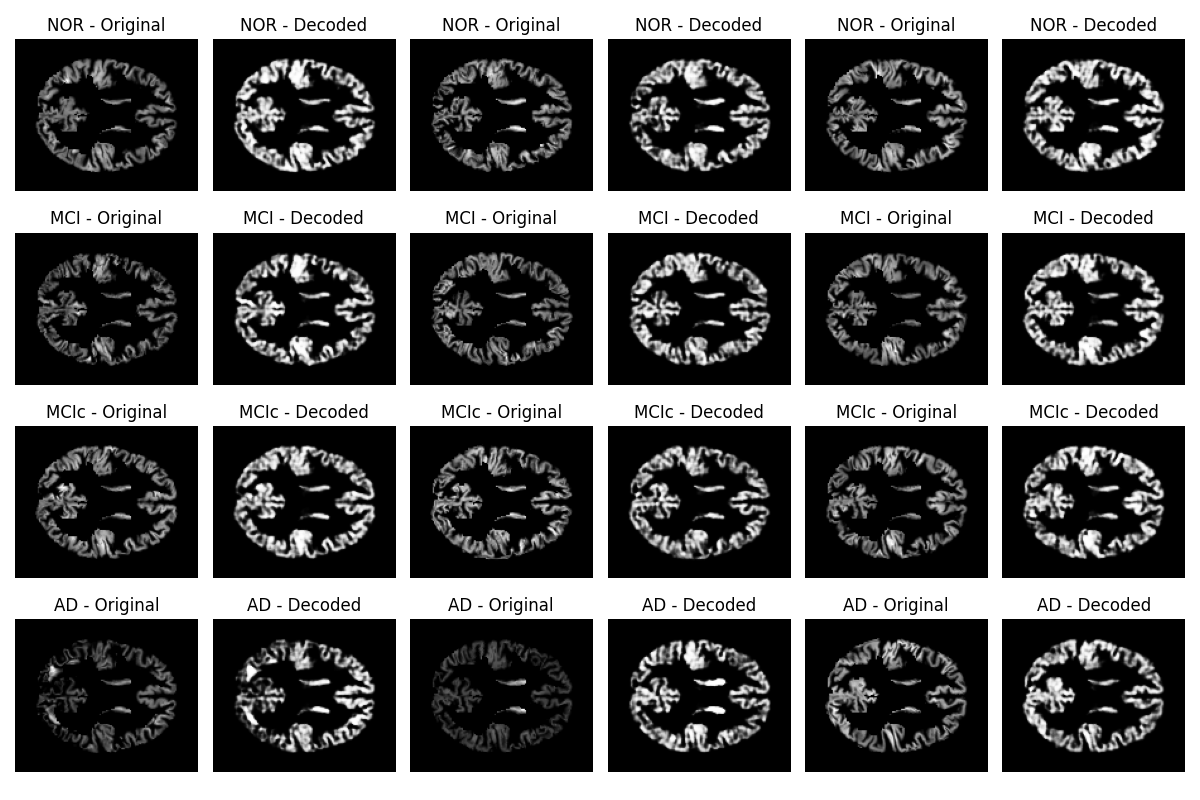

Input images were segmented GM maps derived using the CAT12 [36] toolbox for SPM12 [37]. Unlike full volumetric brain scans, these images represent only the distribution of GM tissue constituting a subset of the full voxel space. As a result, the AE is trained and evaluated on anatomically constrained data, focusing specifically on regions relevant for morphological analysis. Although the original T1-weighted MRI scans had a resolution of 121 × 145 × 121 voxels, the effective number of voxels involved in the reconstruction loss was significantly smaller, limited to those classified as GM by the CAT12 segmentation pipeline. This spatial sparsity increases the interpretability of the reconstruction loss, as the model was optimized to preserve the structure of clinically meaningful brain tissue (see figure 4).

Given that CAT12 GM images represent GM concentrations or volumes that are not normalized, the mean squared error (MSE) values should be interpreted accordingly. In this context, achieving an MSE consistently below 0.01 after 10 training epochs indicates a very low voxel-wise squared difference between original and reconstructed GM maps reflecting a high similarity. A lower MSE thus corresponds to more accurate reconstructions; that is, the AE effectively preserved the anatomical detail of the GM tissue.

The consistently low MSE indicated that the encoder had successfully learned a compact latent representation capable of reconstructing the essential structural features of GM distribution. This latent space can therefore be meaningfully analyzed in relation to standardized brain regions, such as those defined by the AAL atlas. As the reconstruction process was restricted to GM voxels—where neurodegenerative effects are often most pronounced—the learning signal was more focused and anatomically specific. Consequently, achieving MSE values consistently below 0.01 supports the model’s capacity to encode diagnostically relevant morphological information in a class-sensitive latent space, reinforcing its suitability for subsequent anatomical correlation analyses and group-level comparisons.